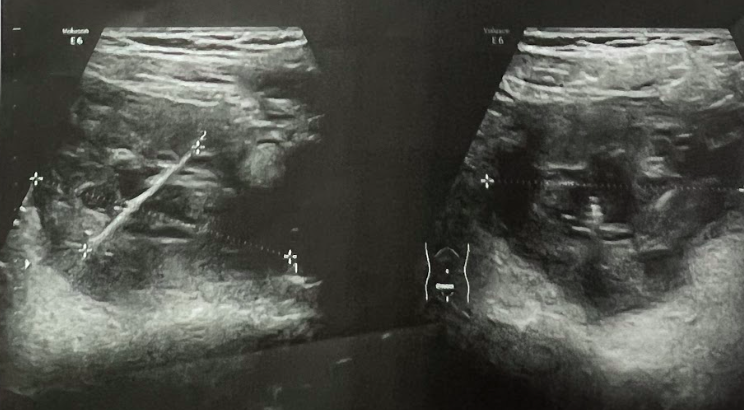

Cụ thể, nữ bệnh nhân quê Vĩnh Phúc ban đầu được chẩn đoán viêm phần phụ. Sau đó đến Bệnh viện Phụ sản Trung ương (Hà Nội), kết quả siêu âm thấy có dị vật trong ổ bụng, lập tức được chuyển đến Bệnh viện Việt Đức.

Tại đây, bệnh nhân được các bác sĩ thăm khám, chụp cắt lớp vi tính, thấy có dị vật trong ổ bụng kích thước 3cm và bụng nhiều dịch mủ, dịch tiêu hóa nhiễm trùng ổ bụng.

Bệnh nhân được phẫu thuật cấp cứu bằng phương pháp nội soi kết hợp mổ mở, lấy ra một dị vật dài 3cm nhọn 2 đầu bằng tre, khâu lại lỗ thủng ruột, rửa sạch mủ và dịch tiêu hoá trong ổ bụng.

Trên phim chụp cắt lớp vi tính cho thấy hình ảnh dị vật hình que dài khoảng 3cm nằm ở đoạn D2 tá tràng. Bệnh nhân được chỉ định nội soi dạ dày tá tràng gây mê lấy dị vật.